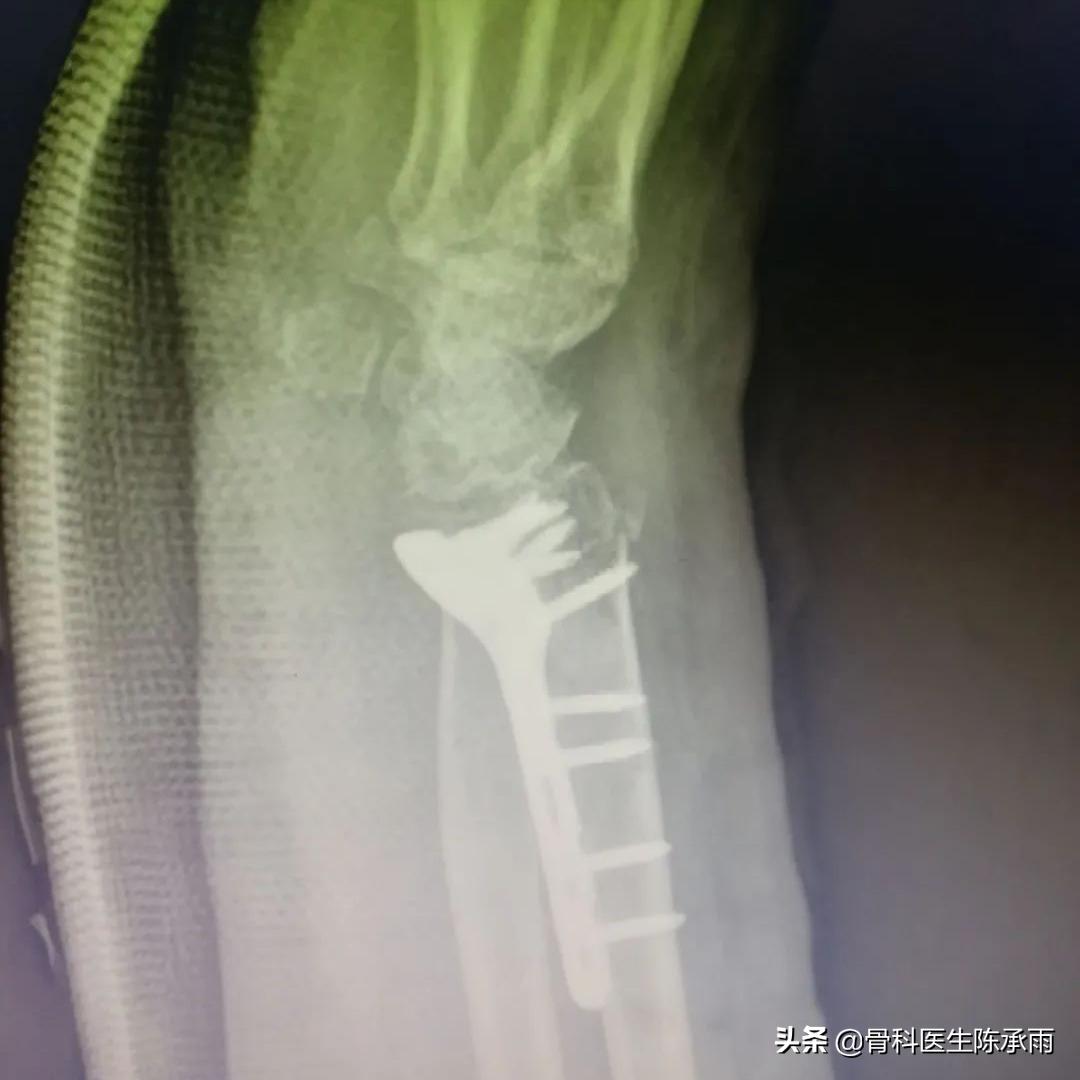

制定手术方案,术中见骨折愈合稳定,骨质疏松严重,远尺桡关节脱位固定,腕关节旋转受限。

原有骨折关系已不能找到,软组织粘连严重,骨折较疏松,尽量达到功能复位。

术后患者恢复良好,患者满意,终于露出久违的笑容。